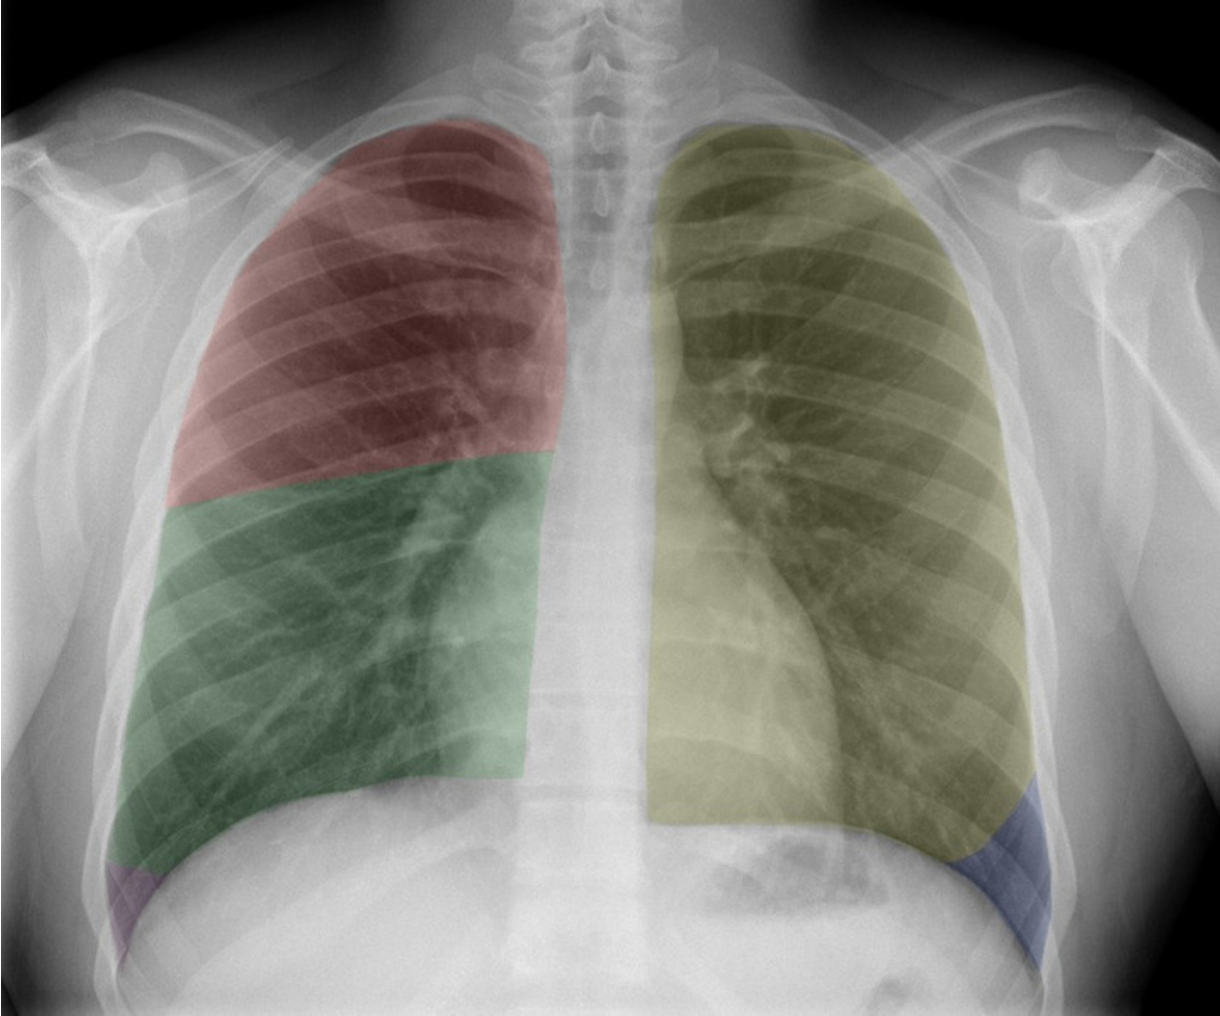

Name the lung lobes according to color

Red = RUL

Green = RML

Purple = RLL (not seen in picture)

Yellow = LUL

Blue = LLL